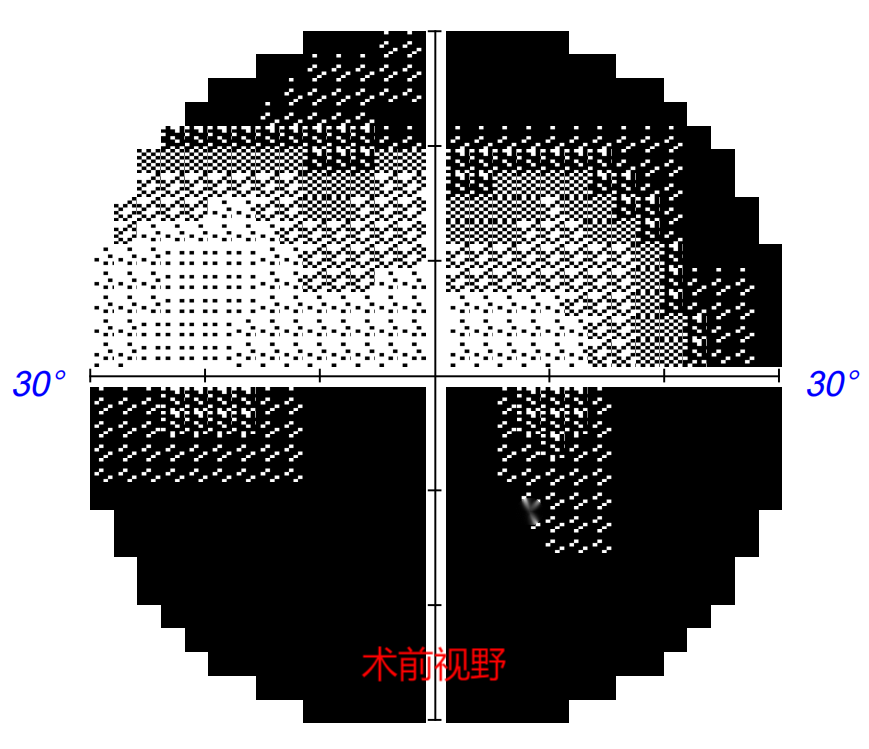

术后1周,张先生的视力恢复至矫正0.5。张先生感慨:就像手机“花屏”修复为清晰流畅的画面。